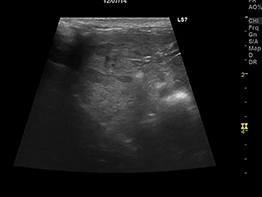

半年前から肝酵素の上昇が見られており、徐々に食欲が落ちてきたワンちゃんの肝臓の超音波所見です。

肝臓が全体的に粗雑になっており、滑らかさがなくなっていました。高齢なのでお腹を開けての肝臓のバイオプシーは負担がかかってしまう、負担をなるべく軽くしてあげたい、との飼い主様のご希望で当院の腹腔鏡下肝バイオプシーを実施しました。